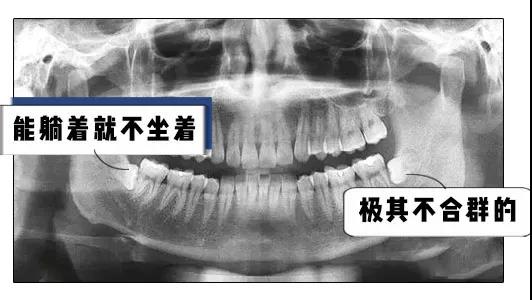

它不好好长就算了

长的不好还骚扰隔壁邻居

这种智齿是必须要拔掉才可以的